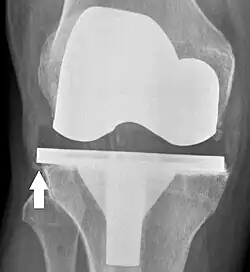

Knee replacement is routinely evaluated by X-ray, including the following measures:

![HKA: Hip-knee-ankle angle, which is ideally between 3° varum to 3° valgum from a right angle.[62]](./_assets_/X-ray_of_HKA_angle_with_knee_prosthesis.jpg)

- FFC: frontal femoral component angle. It is typically regarded as optimal when being 2–7° in valgus.[63]

- FTC: frontal tibial component angle, which is regarded as optimal when being at a right angle. A varus position of more than 3° has generally been found to increase the failure rate of the prosthesis.[63] -

- Anterior femoral notching (the femoral component causing reduced thickness of the distal femur anteriorly), seems to cause an increased risk of fractures when exceeding about 3 mm.[64]

- LTC: lateral (or sagittal) tibial component angle, which is ideally positioned so that the tibia is 0–7° flexed compared to at a right angle with the tibial plate.[63]